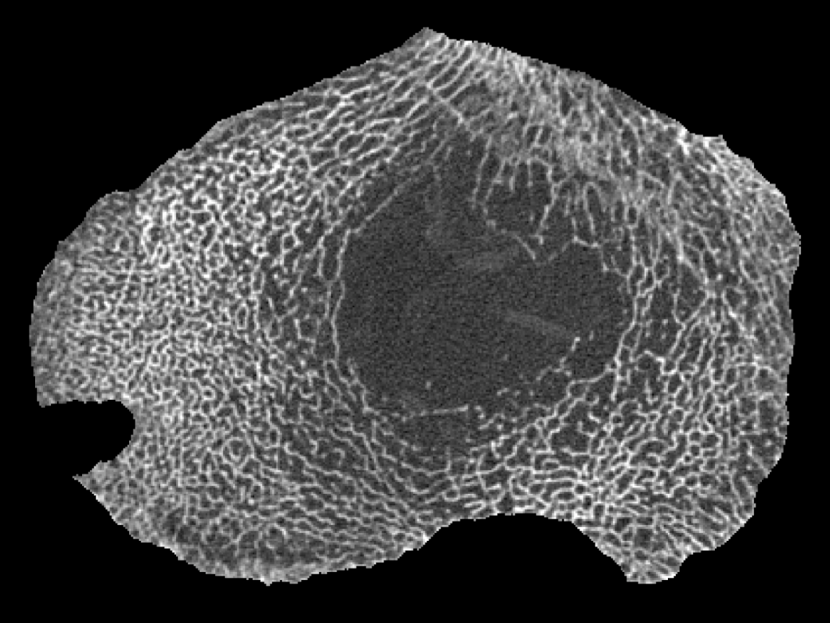

For each proximal tibia, an axial QCT slice was acquired 17 mm below the tibial plateau with a Stratec XCT-2000 pQCT scanner (Stratec GmbH, Pforzheim, Germany), with an in-plane pixel size of 200 m 200 m and a slice thickness of 1 mm. In some cases, the scans were performed after the biopsies were taken. Therefore, the holes left from the bone biopsy appear in some of the pQCT images. A standardised image pre-processing procedure was applied to exclude the cortical shell from the analysis. Saparin et al. (1998); Saparin, Gowin, and Felsenberg (2002); Saparin et al. (2006) One of the resulting images is shown in Fig. 1.

III.6 Illustration

To illustrate the analytical method, we now present the results in visual form for an enlarged region near the bottom (posterior) of the slice in Fig. 1. The enlarged region of the original image is shown in Fig. 3(a). Parts (b) to (e) of Fig. 3 show directional strand strengths, and part (f) shows the final node strength plot. Each directional strand strength plot shows the sum of two strand strengths at every pixel, in opposite directions: east/west; north/south; northwest/southeast; and northeast/southwest. In each of the directional strand strength plots, the strands in the given direction are shown with the highest intensity, but most of the trabeculae are still visible, even if faintly. In contrast, in the node strength plot (part (f)), most of the trabeculae are invisible. This is because of the subtraction of the minimum strength constant. In this example, there are almost no nodes in the right half of the image. This correctly describes the micro-architecture of the original image in that region, which contains many trabeculae but few that cross each other to make a lattice-like micro-architecture. The left half of the image contains many nodes. Notice that, in the node strength plot, the nodes seem to be thicker than in the original image. This is because the trabeculae in the original image are actually slightly thicker than they appear, the outer pixels being dimmer (i.e. lower CT values) and thus not easily registered by the eye. Since the outer pixels near the apparent nodes in the original image are almost as well-connected as pixels in the centres of the nodes, they have large node strengths, and are very visible in the node strength plot.

The two specimens depicted in Figs. 4 and 5 have comparable bone mineral densities, but their trabecular micro-architecture are visibly different. In Fig. 4, the specimen has a trabecular BMD of 107 mg/cm3, which is near the median value (97 mg/cm3) of the specimens in this study. On the left is the original image, and on the right is the node strength plot. Notice that there are a lot of nodes in most of the outer areas, with the notable exception of a region near the bottom left. The mean node strength is 71.2.

The specimen in Fig. 5 has a trabecular BMD of 94 mg/cm3, which is only 12% lower than that of the specimen shown in Fig. 4, but it has substantially fewer nodes. The mean node strength is only 42.2, which is 40% lower than that for the specimen shown in Fig. 4. This reflects the lack of a strong lattice-like micro-architecture in the original image.